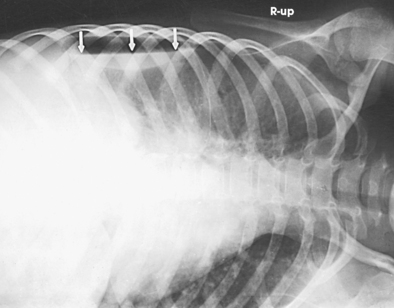

Fig. 10-8 A, PA chest radiograph showing mediastinal enlargement caused by hypertrophy of thymus (arrows). B, Lateral chest radiograph showing enlarged thymus (arrow).

In older individuals, lymphatic tissue is replaced by fat. At its maximum development, the thymus rests on the pericardium and reaches as high as the thyroid gland. When the thymus is enlarged in infants and young children, it can press on the retrothymic organs, displacing them posteriorly and causing respiratory disturbances. A radiographic examination may be made in the AP and lateral projections. For optimal image contrast, exposures should be made at the end of full inspiration.